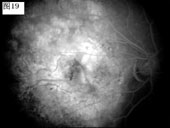

[组图]优秀眼底图片奖网上评选活动启动         ★★★

优秀眼底图片奖网上评选活动启动

优秀眼底图片奖应征作品展示